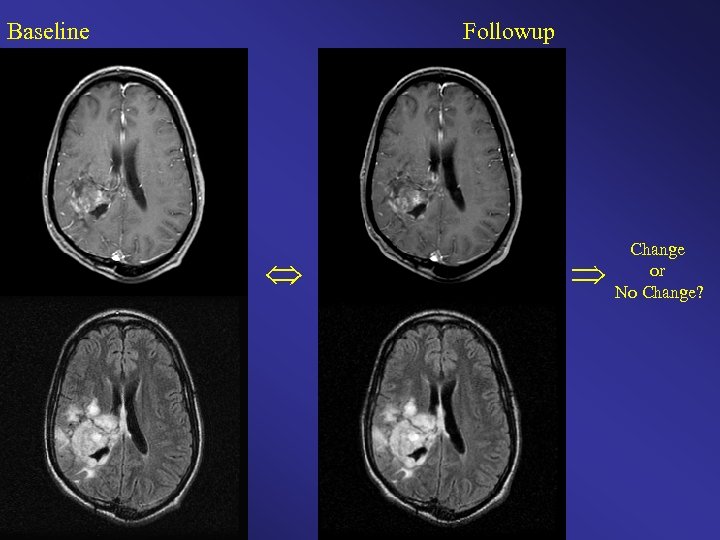

Baseline Follow-up Change or No Change?

Other reasons radiologists might miss changes: Satisfaction of Search Change occurs in an unexpected location Change is in a sub-part of a complicated lesion Etc.